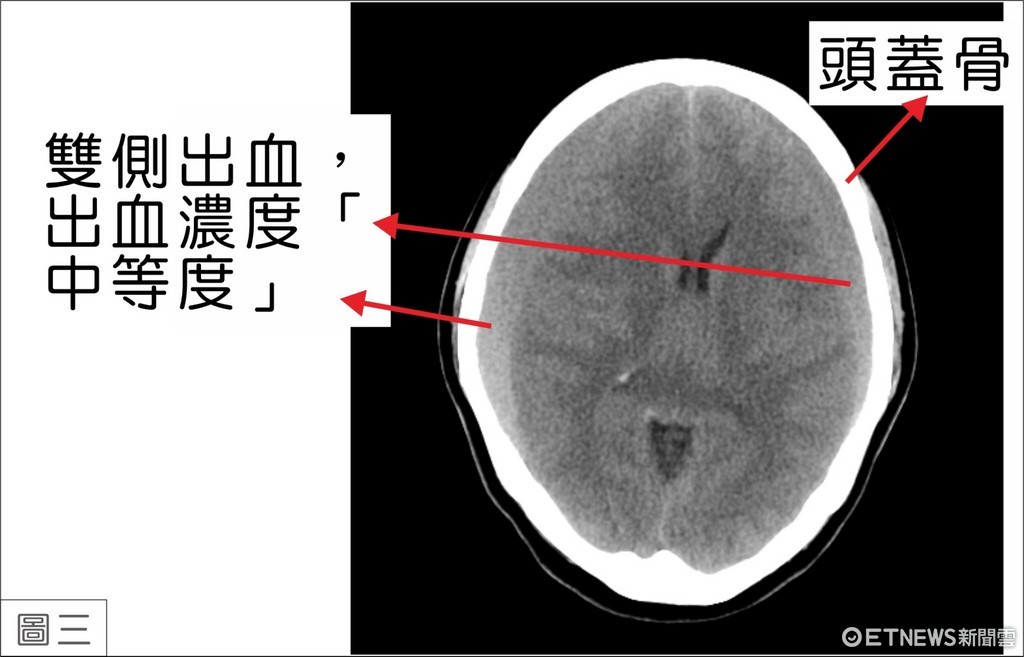

江明哲醫師表示:「這種兩側發生血腫的病例,有時很難早期被發現。其症狀就像感冒一樣,頭痛、嘔吐、身體乏力、步態不穩、頭頸部僵硬。在電腦斷層檢查中,濃度高的血水會呈現白色彎月狀影像,很容易被發現而接受手術治療。但是陳女士的出血濃度是「中等度」,同時又在顱內兩側發生,電腦斷層就不容易區別而被忽略(圖三)。」經詳問陳女士家屬,得知陳女士在住院前六個月,因跌倒而頭部受到撞擊。